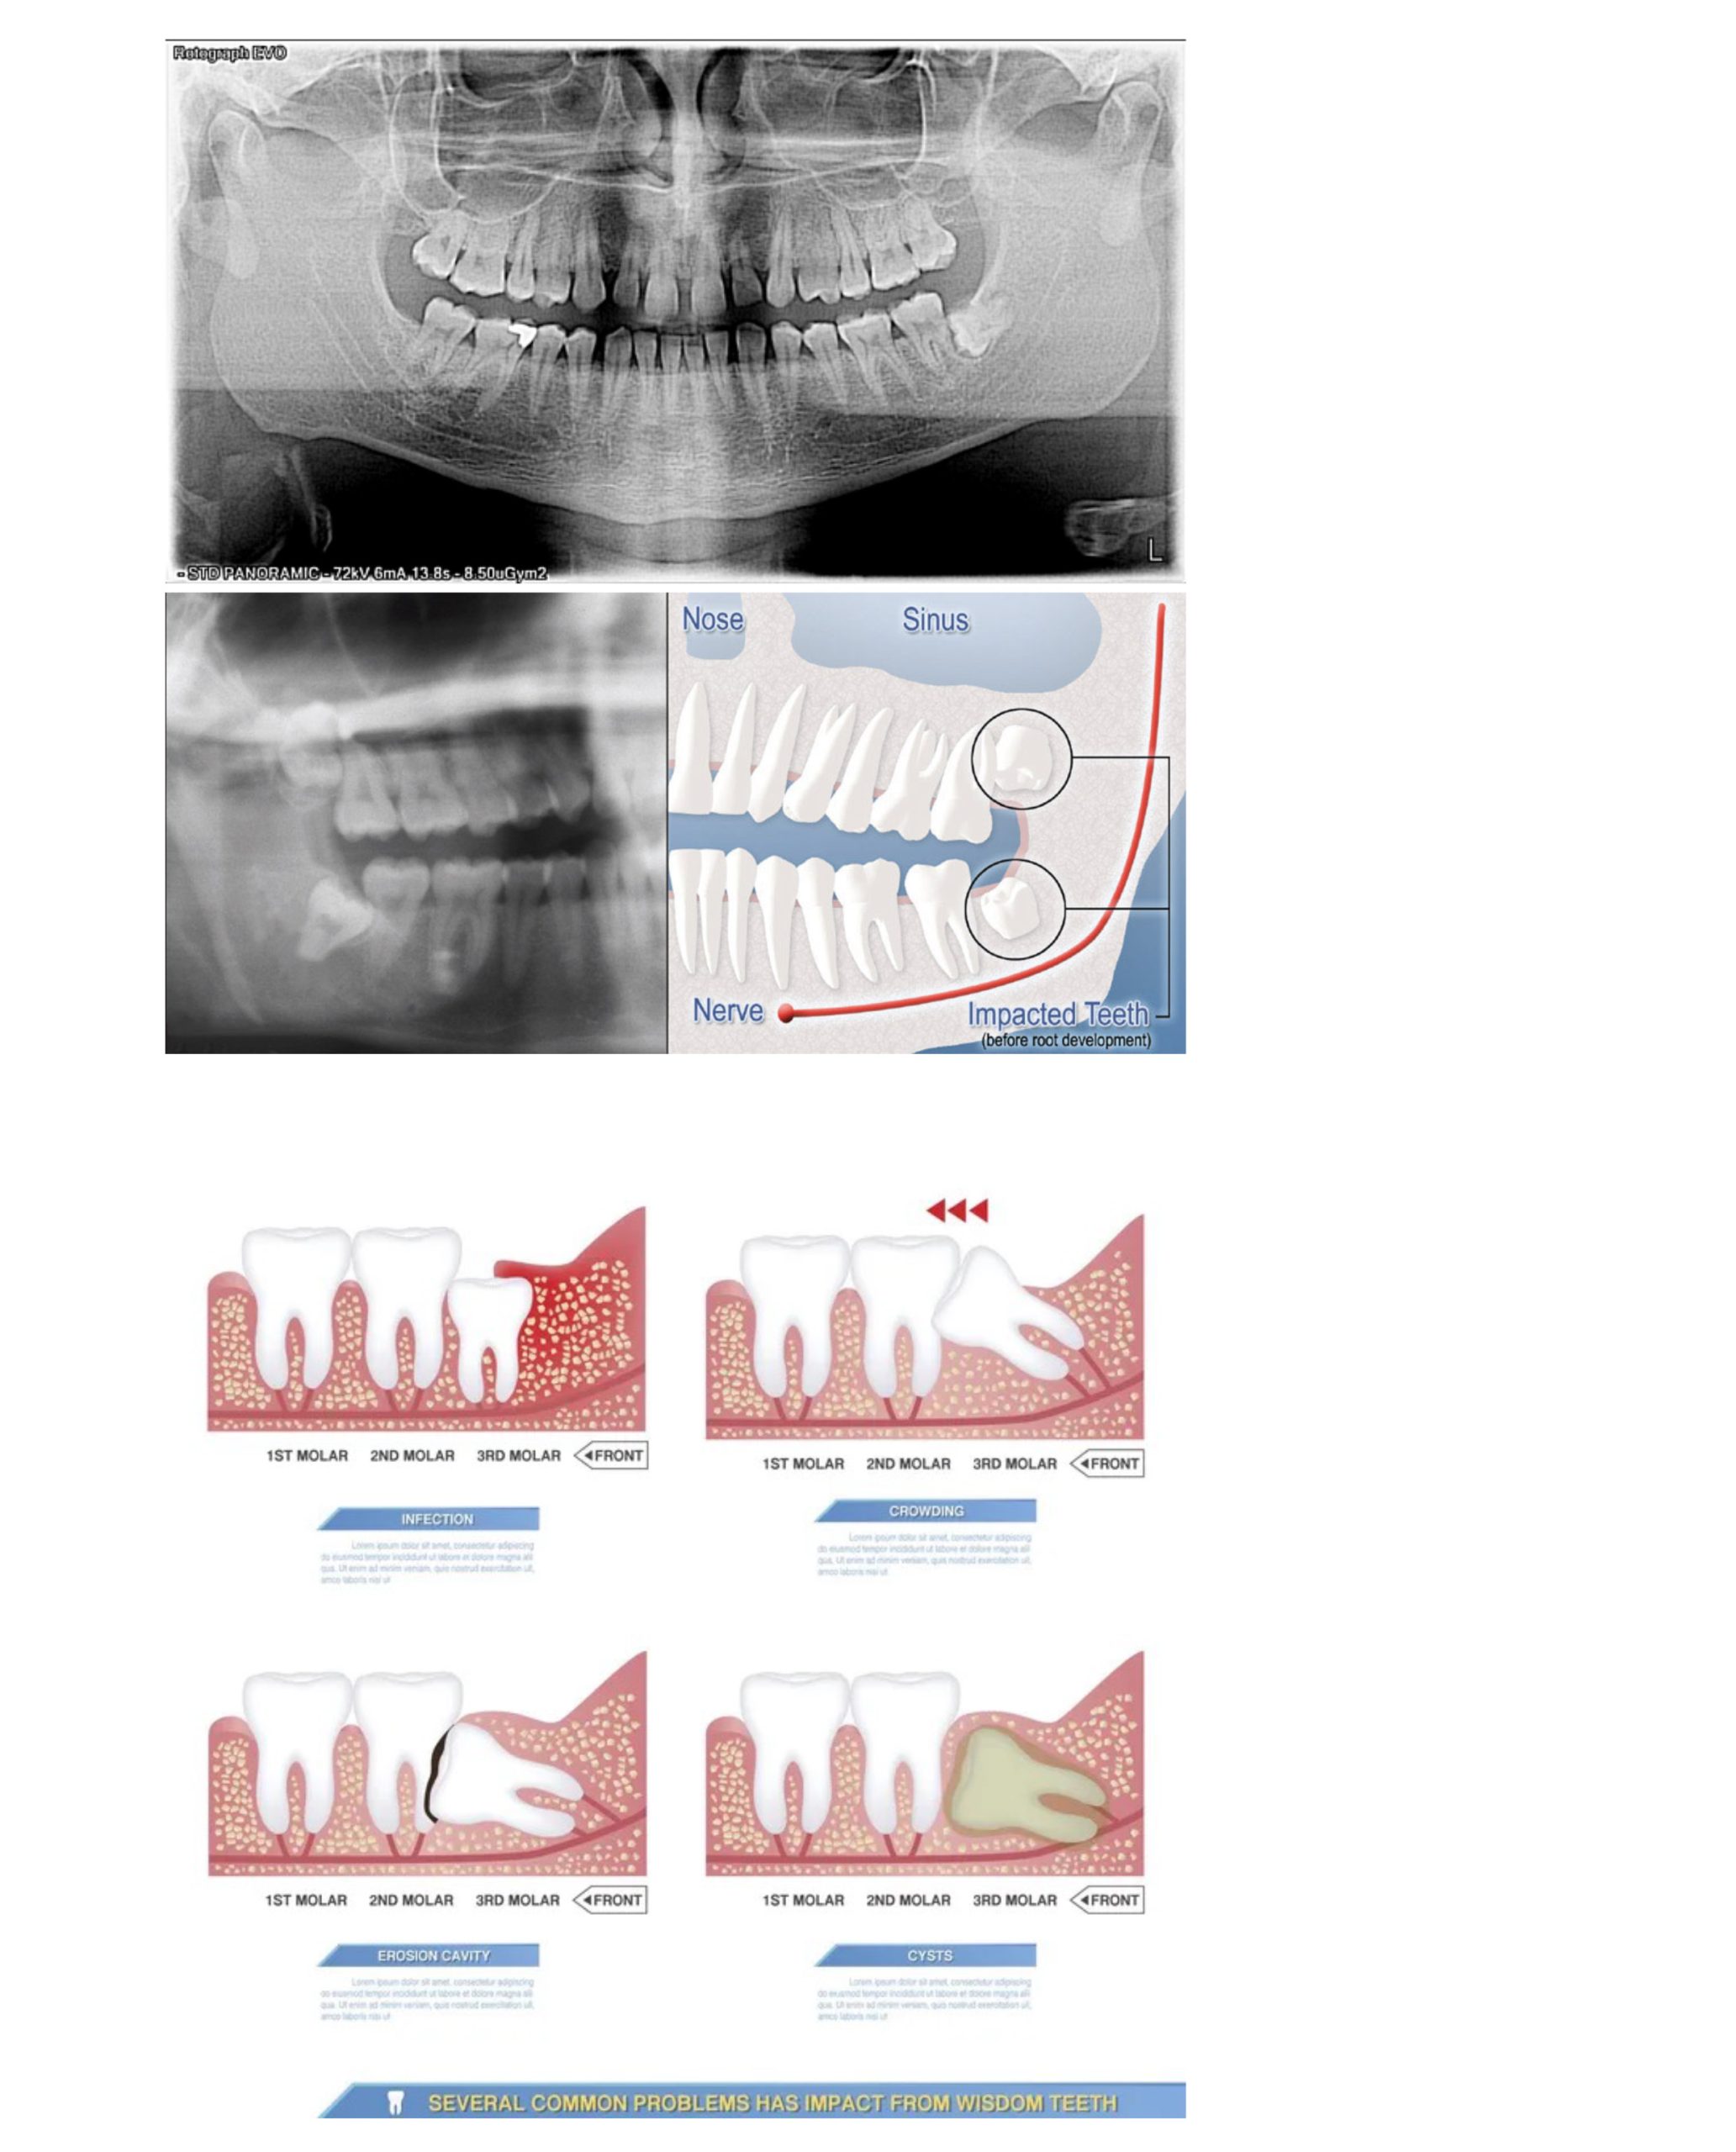

धेरै अक्ल दाँत जबडामा पर्याप्त ठाउँ नभएकाले ठीकसँग उम्रन सक्दैनन् । यदि यी दाँतहरु रहिरहे भने सम्भावित समस्याहरुः

—दाँतमा किरा लाग्नु (टुथ डिके)

—गिँजामा संक्रमण (पेरिकोरोनाइटिस)

—छेउका दाँतमा क्षति

—सिष्ट वा हड्डीमा क्षति